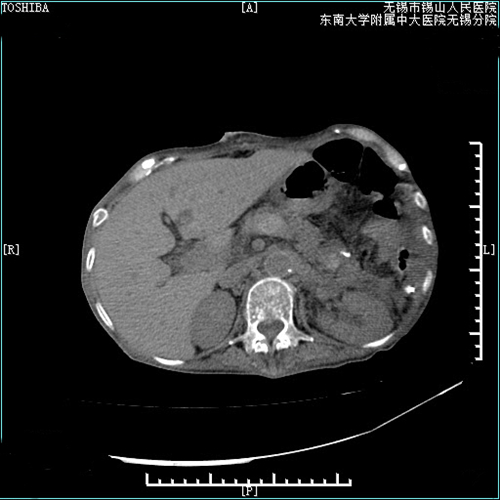

一月前,张阿姨皮肤黏膜多处瘀点瘀斑,牙龈出血,食纳下降,明显消瘦,并伴有口腔黏膜溃烂等症状。张阿姨在家人的陪同下来院就诊。血液肿瘤科主任张世强和副主任强金虎接诊后,将张阿姨收住入院,进一步检查后发现,张阿姨一度被外院诊断为“骨髓增生异常综合征(MDS)”,这一诊断引起了肿瘤血液科张世强主任和强金虎的注意。肿瘤血液科医疗团队组织了心内科、消化内科、肝胆外科、血管介入科、影像科等部门,开展MDT多学科会诊。结合患者的血液学、影像学等检查结果,普外科副主任兼肝胆外科副主任赵万文考虑患者为血吸虫肝病后的脾功能亢进,进行性导致脾大(Ⅲ度肿大),引起血液系统的明显改变(类白血病现象)。

随后,张阿姨转到了肝胆外科,开始完善术前准备。普外科医疗团队组织了科内疑难病重病理讨论。顾盐炎主任解析了血吸虫肝病的相关知识,针对患者病因、病情、诊断、影像资料、治疗策略等多方面进行分析指导,制定了周密的手术方案。